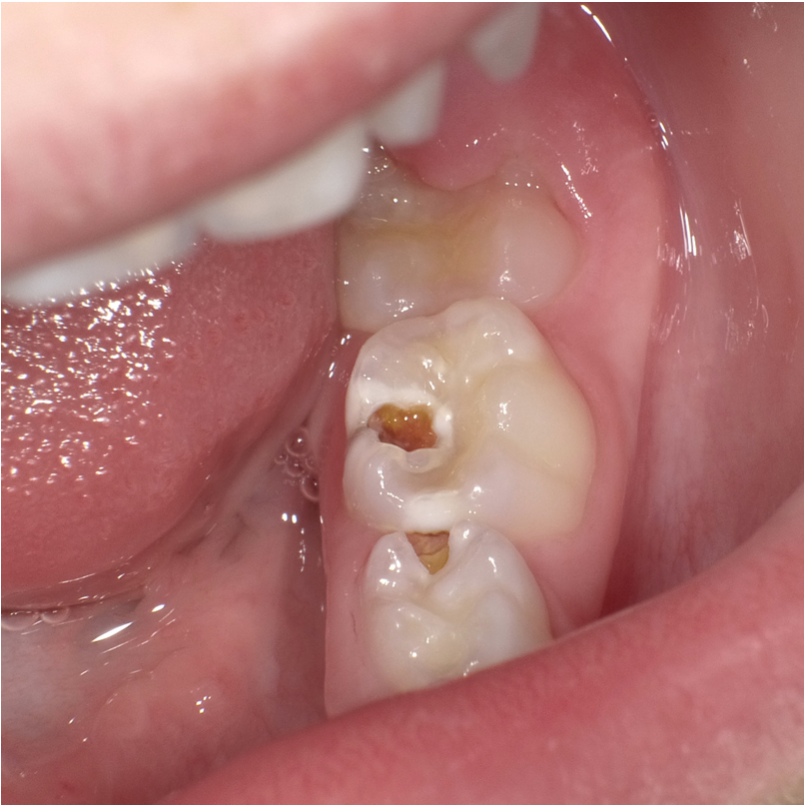

På billedet kan vi se

1. Den sunde overflade (sund emalje)

2. Begyndende hul (ætset emalje)

3. Brud på overfladen og skade på vævet dybere inde i tanden. Nu er der et egentligt hul i tanden, som kræver en fyldning.